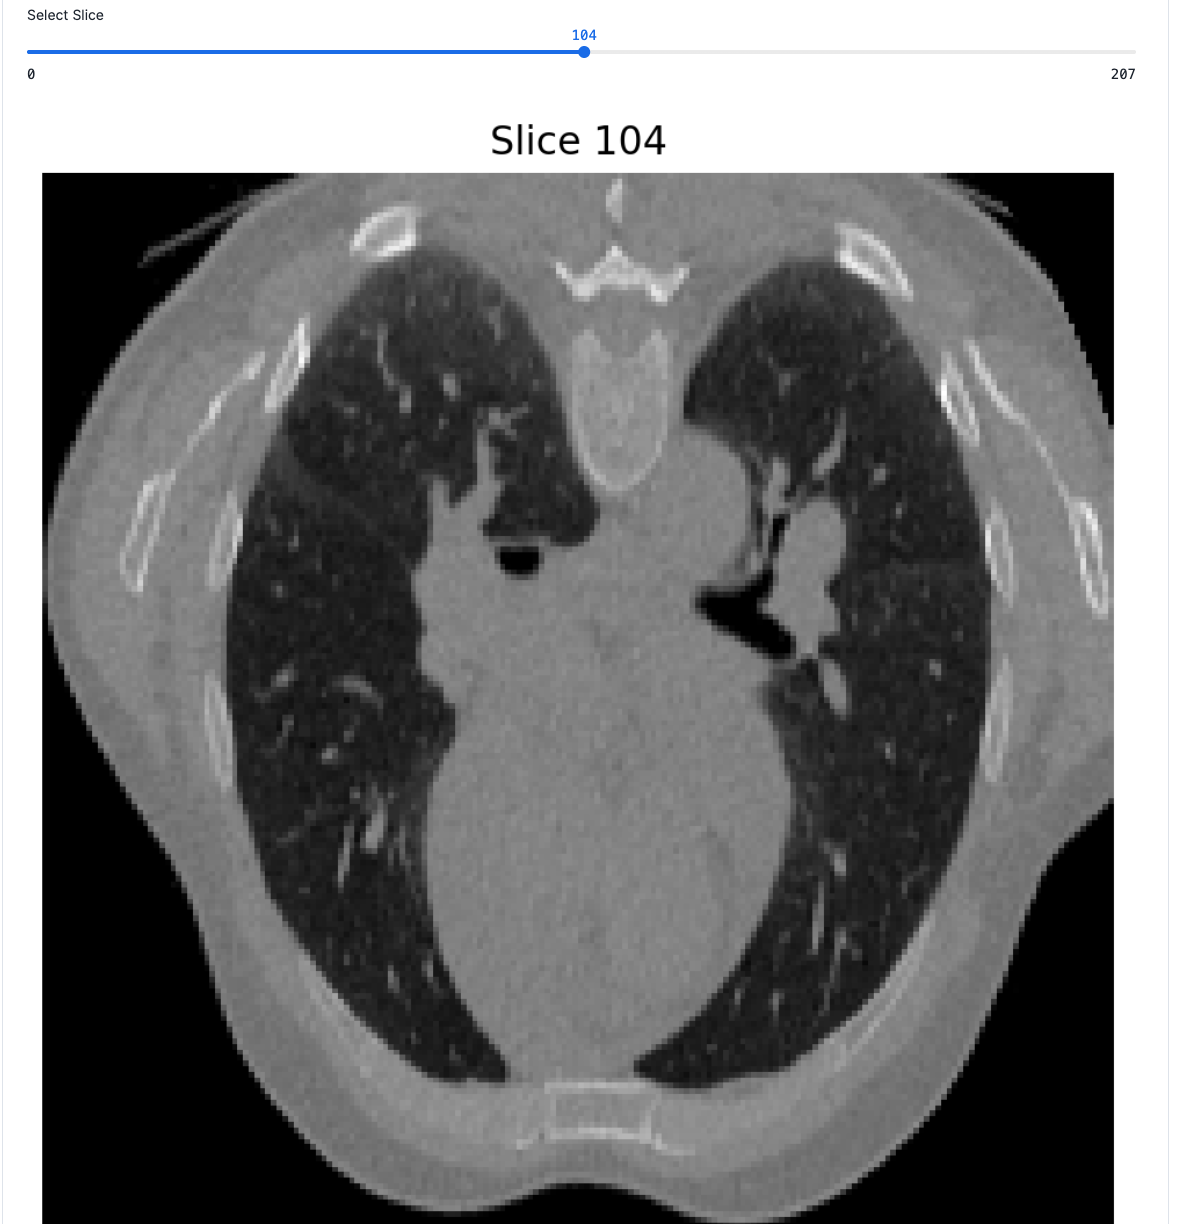

The notebook also includes interactive CT scan visualization to inspect the training data: